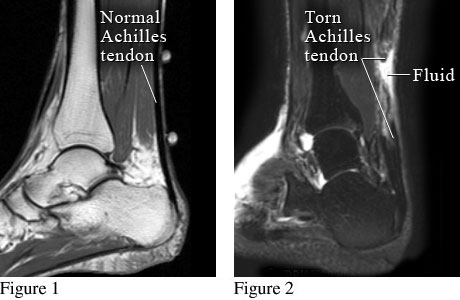

Achilles Tendon Injury